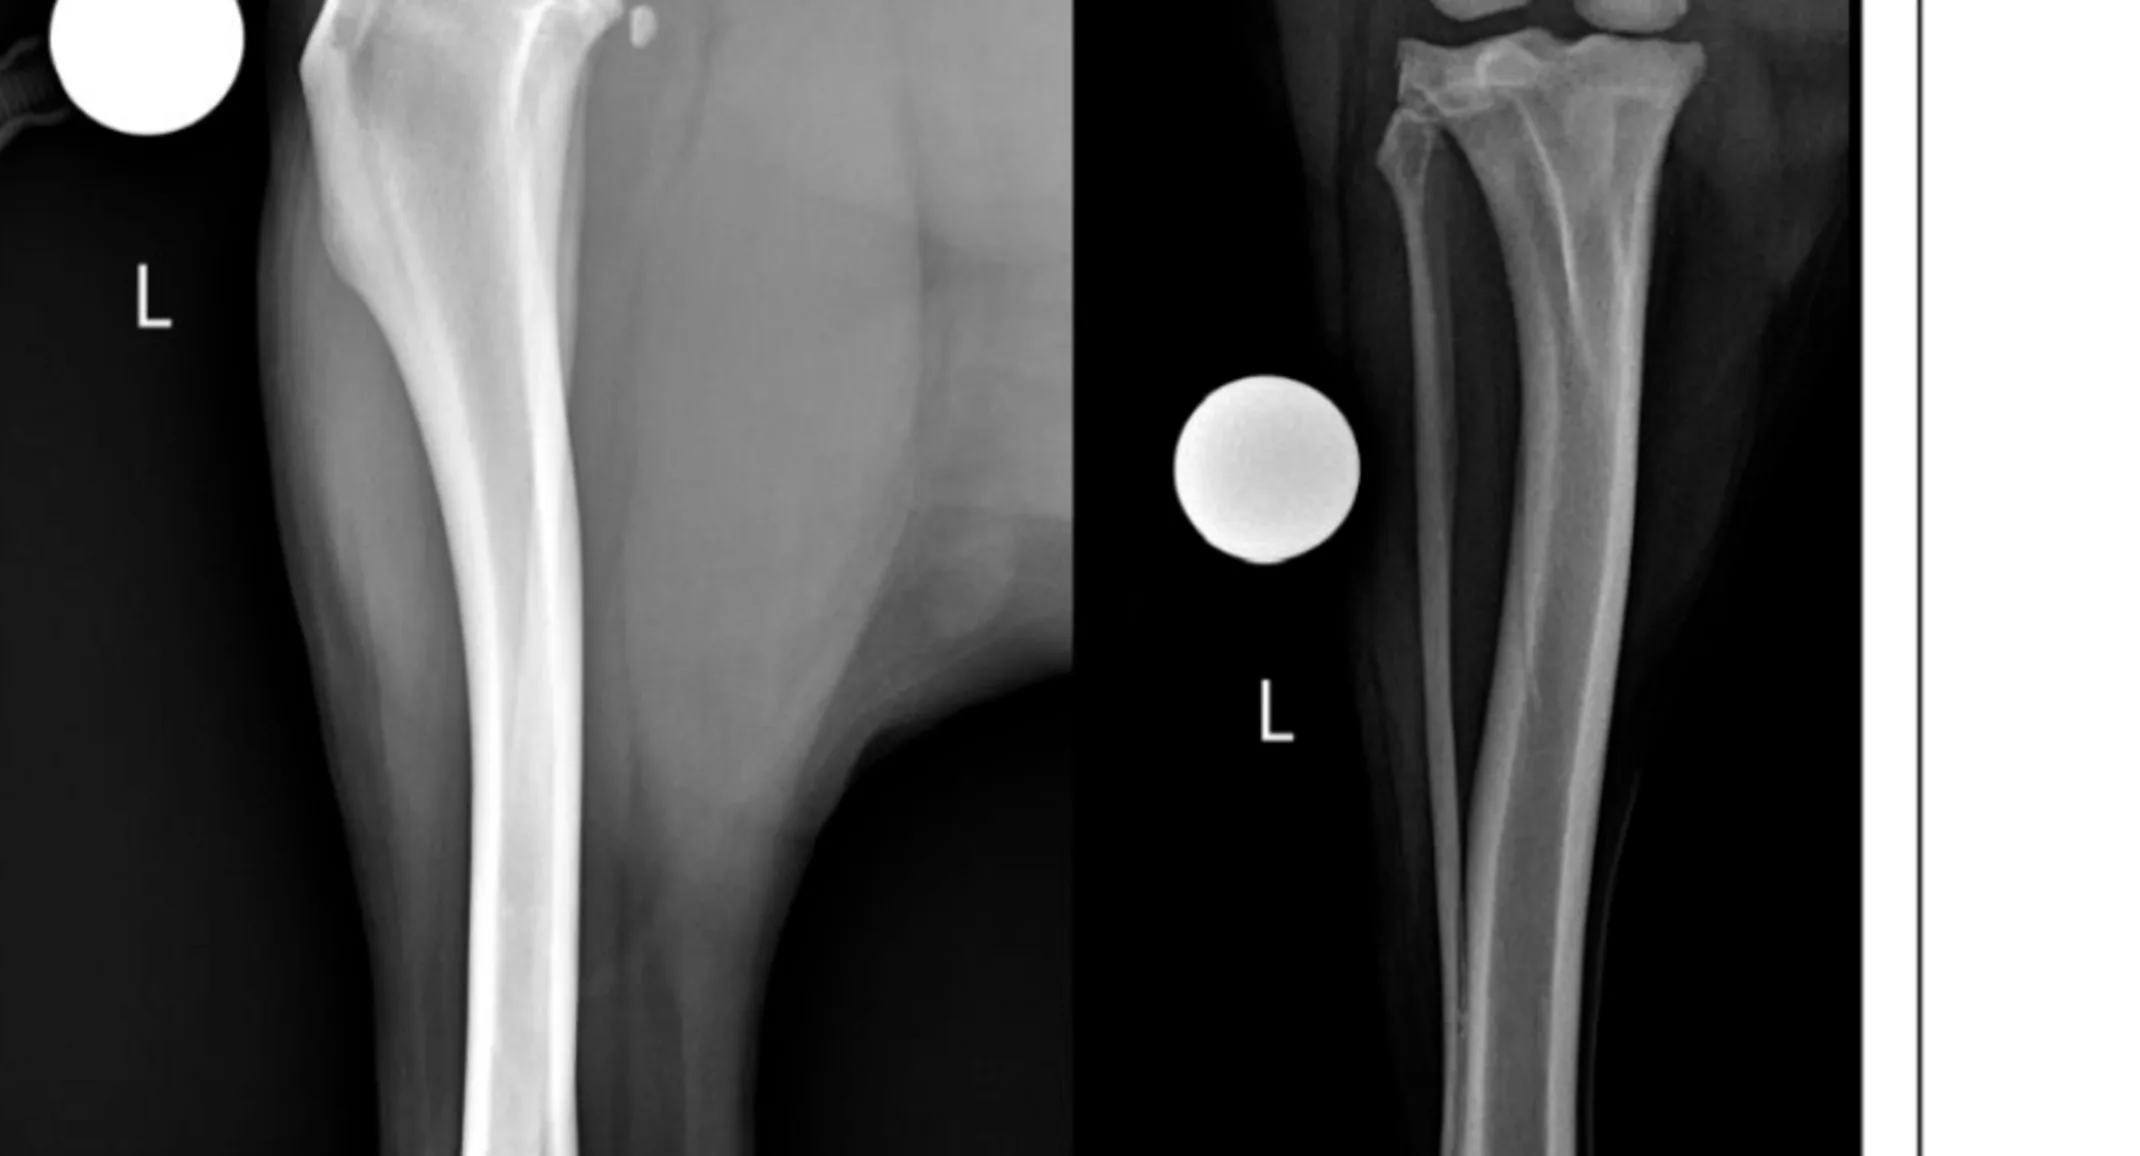

A fine needle aspirate and cytology of the left forelimb mass were performed and were consistent with a lipoma. A routine complete blood count and chemistry panel were performed and were unremarkable. Radiographs were performed of the left stifle (Figure 1), which revealed moderate to significant intracapsular soft tissue opacity (consistent with joint effusion), very mild osteophytosis at the proximal aspect of the femoral trochlear ridges and the insertion site of the cranial cruciate ligament (CCL) on the tibial plateau, as well as moderate cranial tibial subluxation. No other concerning changes were noted.

Figure 1